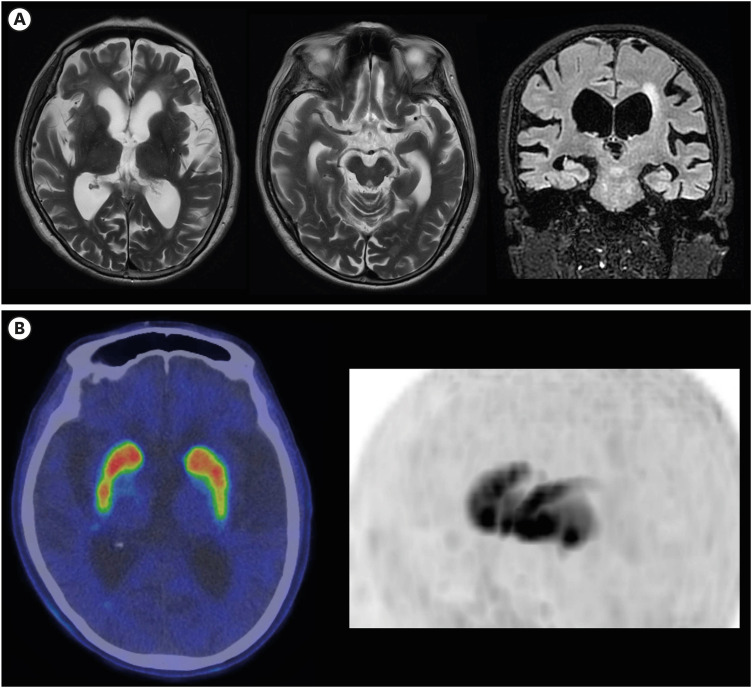

Shunt-Responsive Idiopathic Normal Pressure Hydrocephalus Patient With Parkinson's Disease-Compatible Findings on Dopamine Transporter Scans.